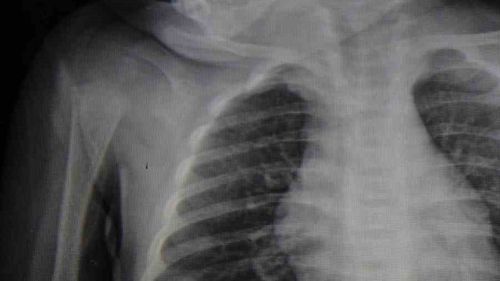

Karaman'da 6 aylık E.A.'nın boğazına kaçan kumanda pili ameliyatla çıkarıldı Karaman Eğitim ve Araştırma Hastanesi acil servisine kusma şikayetiyle getirilen 6 aylık E.A.'nın boğazında yapılan muayene ve tetkiklerde kumanda pili tespit edildi. Solunum sıkıntısı yaşayan bebek, Çocuk Cerrahisi Uzmanı Doç.…